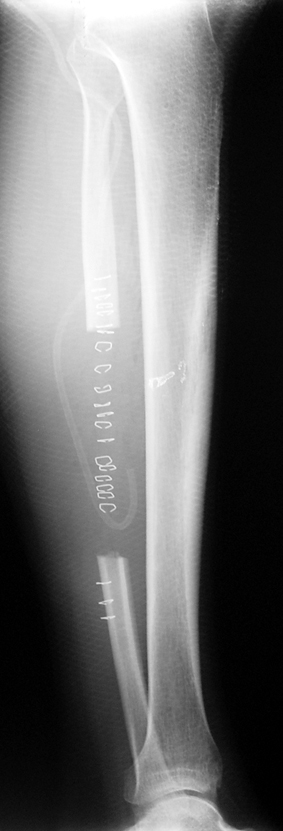

Eksternal fiksatör ile geçen süre (eksternal fiksasyon indeksi), gereken distraksiyon miktarına bağlıdır ve bu süre boyunca bazı komplikasyonlarla karşılaşılabilir. Distraksiyon dönemi sona erdikten sonra, distraksiyon süresinin iki katını aşan konsolidasyon döneminde hastalar eksternal fiksatörü zorlukla tolere edebilirler. Yeterli konsolidasyon sağlanmadan eksternal fiksatör çıkartılırsa ise kırıklar, deformite ve kısalık oluşabilir. Hastanın fiksatör ile birlikte geçirdiği sürenin azaltılması ve böylece hasta konforunun ve aktivite düzeyinin arttırılması için intramedüller çivi üzerinden uzatma yöntemi uygulanmaktadır. Bu yöntemde distraksiyon dönemi sona erdiğinde kemiğin içindeki çivi statik olarak kilitlenmekte ve eksternal fiksatör çıkartılmaktadır. Stabilizasyon intramedüller çivi tarafından sağlandıktan sonra konsolidasyon dönemi gerçekleşmektedir. Bu şekilde hem eksternal fiksatörün uzun süre kalmasından hem de erken çıkartılmasından kaynaklanan komplikasyonların önüne geçilmektedir.

Vaka 3